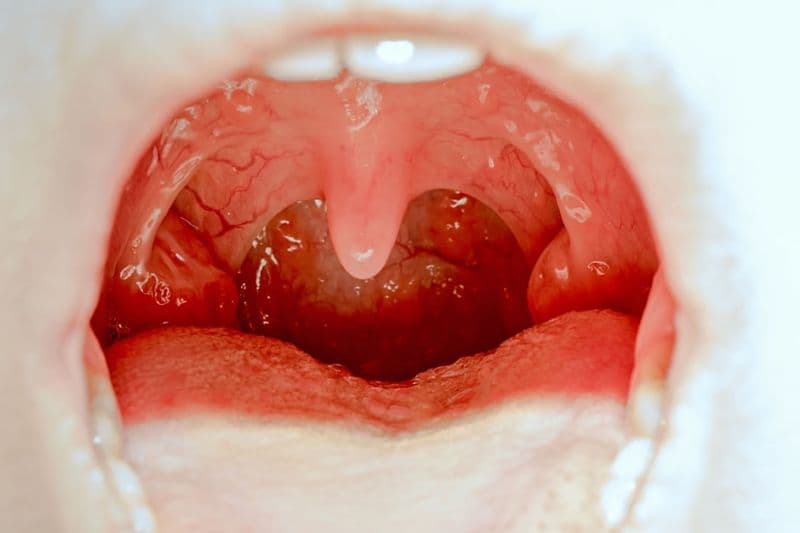

Chảy máu amidan (còn gọi là xuất huyết amidan) là hiện tượng có máu rỉ, đọng cục ở bề mặt amidan hoặc máu lẫn trong nước bọt, đờm xuất phát từ vùng amidan. Tình trạng này có thể gặp khi amidan bị viêm nhiễm, xung huyết, loét; hoặc sau can thiệp phẫu thuật amidan.

Theo nội dung của bác sĩ Karen Grill viết trên Healthline, một số trường hợp amidan nhìn “đỏ như chảy máu” do mạch máu nông giãn, nhưng không thực sự có máu trong nước bọt. Vì vậy, cần phân biệt đỏ, xung huyết với chảy máu thật.